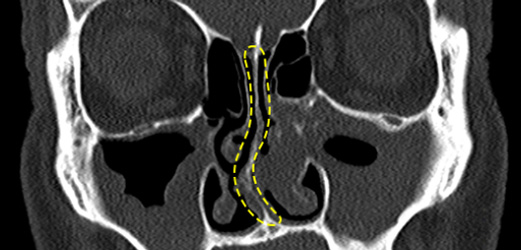

비중격 만곡증

매부리코/휜코의 대부분은 비중격만곡증을 동반하고 있습니다. 비중격만곡증이 심한 경우 코 막힘 , 비염 , 축농증 등의 질병을 유발하여 일상생활에 불편함을 줍니다. 수술 전 비중격만곡증의 유무를 면밀하게 관찰하여 코 라인과 함께 비중격만곡증 개선을 도와 드립니다.

3D-CT로 코 내부 속까지

디테일한 정밀 진단!

수술 전 3D-CT 검사를 통해 육안으로는 확인이 어려운

코 내부의 조직 상태인 골격구조, 코뼈의 넓이, 비중격 상태와

비대칭 여부, 하비갑개 크기 등을 정밀 촬영 후

성형외과전문의와의 상담을 통해 기능개선 여부 유/무를 진단합니다.